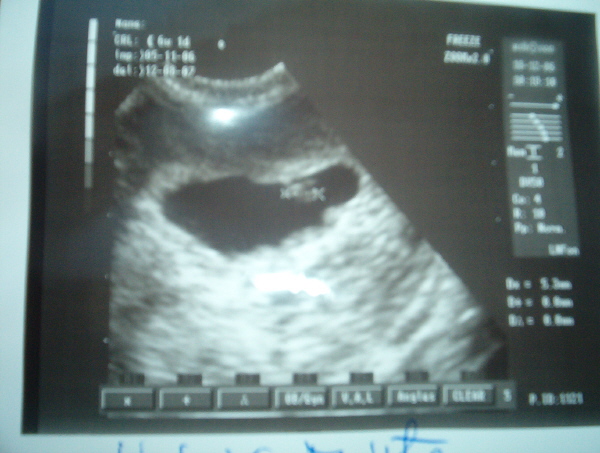

Emma: gratulálok a UH-hoz.

Ahogy olvastam az üziket, láttam, hogy elég sokan megyünk 28-án UH-ra! Remélem, hogy mindannyian jó híreket fogunk kapni. Én már nagyon várom!